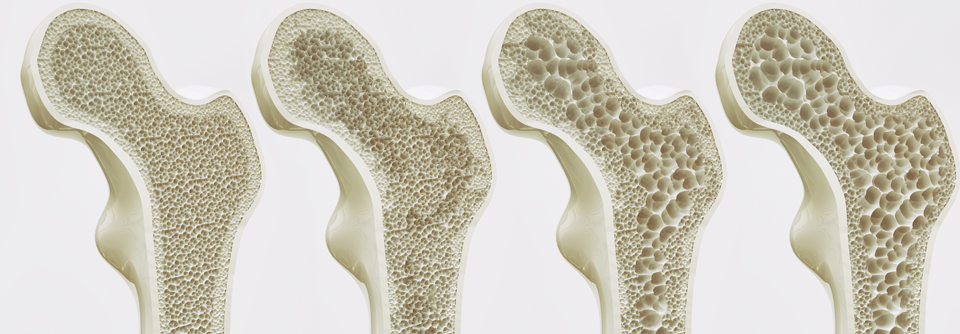

Die Weltgesundheitsorganisation geht davon aus, dass sich die Anzahl der osteoporotischen Knochenbrüche bis 2050 weltweit vervierfachen wird. Die Weltgesundheitsorganisation geht davon aus, dass sich die Anzahl der osteoporotischen Knochenbrüche bis 2050 weltweit vervierfachen wird. © Science Photo Library/Gschmeissner, Steve

Eine niedrige Knochendichte ist in der Regel mit einem höheren Risiko für Knochenbrüche assoziiert. Die meisten Frakturen lassen sich daher per Dual-Röntgen-Absorptiometrie (DXA) vorhersagen. Dennoch ist der damit gemessene Wert (bone mineral density, BMD) allein für das Risikoassessment bei Osteoporose kein guter Marker, schreiben Dr. Friedrike­ Thomasius­ vom Frankfurter Hormon- & Osteoporosezentrum und Dr. Björn Bühring, Rheumazentrum Ruhrgebiet, Herne. Dazu ist die Sensitivität diesbezüglich zu gering, denn weniger als die Hälfte der Frakturen bei älteren Frauen ist mit einer verminderten BMD assoziiert. Genauer gesagt: Die meisten Frakturen ereignen sich oberhalb des Schwellenwerts, der für eine messtechnisch ermittelte Osteoporose gilt.